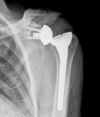

Normal acromiohumeral interval distance? What numbner is considered pathognomoinc for rotator cuff tear? What are findings consistent advanced cuff tear arthropathy?

Normal 7-14, less than 14 is radiographic marker for cuff disease * Acetabularization of the acromion, rounding of the greater tuberosity, and femoralization of the humeral head are signs of advanced rotator cuff arthropathy that can be appreciated on shoulder radiographs. * Chronic rotator cuff insufficiency may result in anterosuperior escape (migration of the humeral head through the rotator interval). This results from failure of the subscapularis and/or supraspinatus (rotator interval lesion).